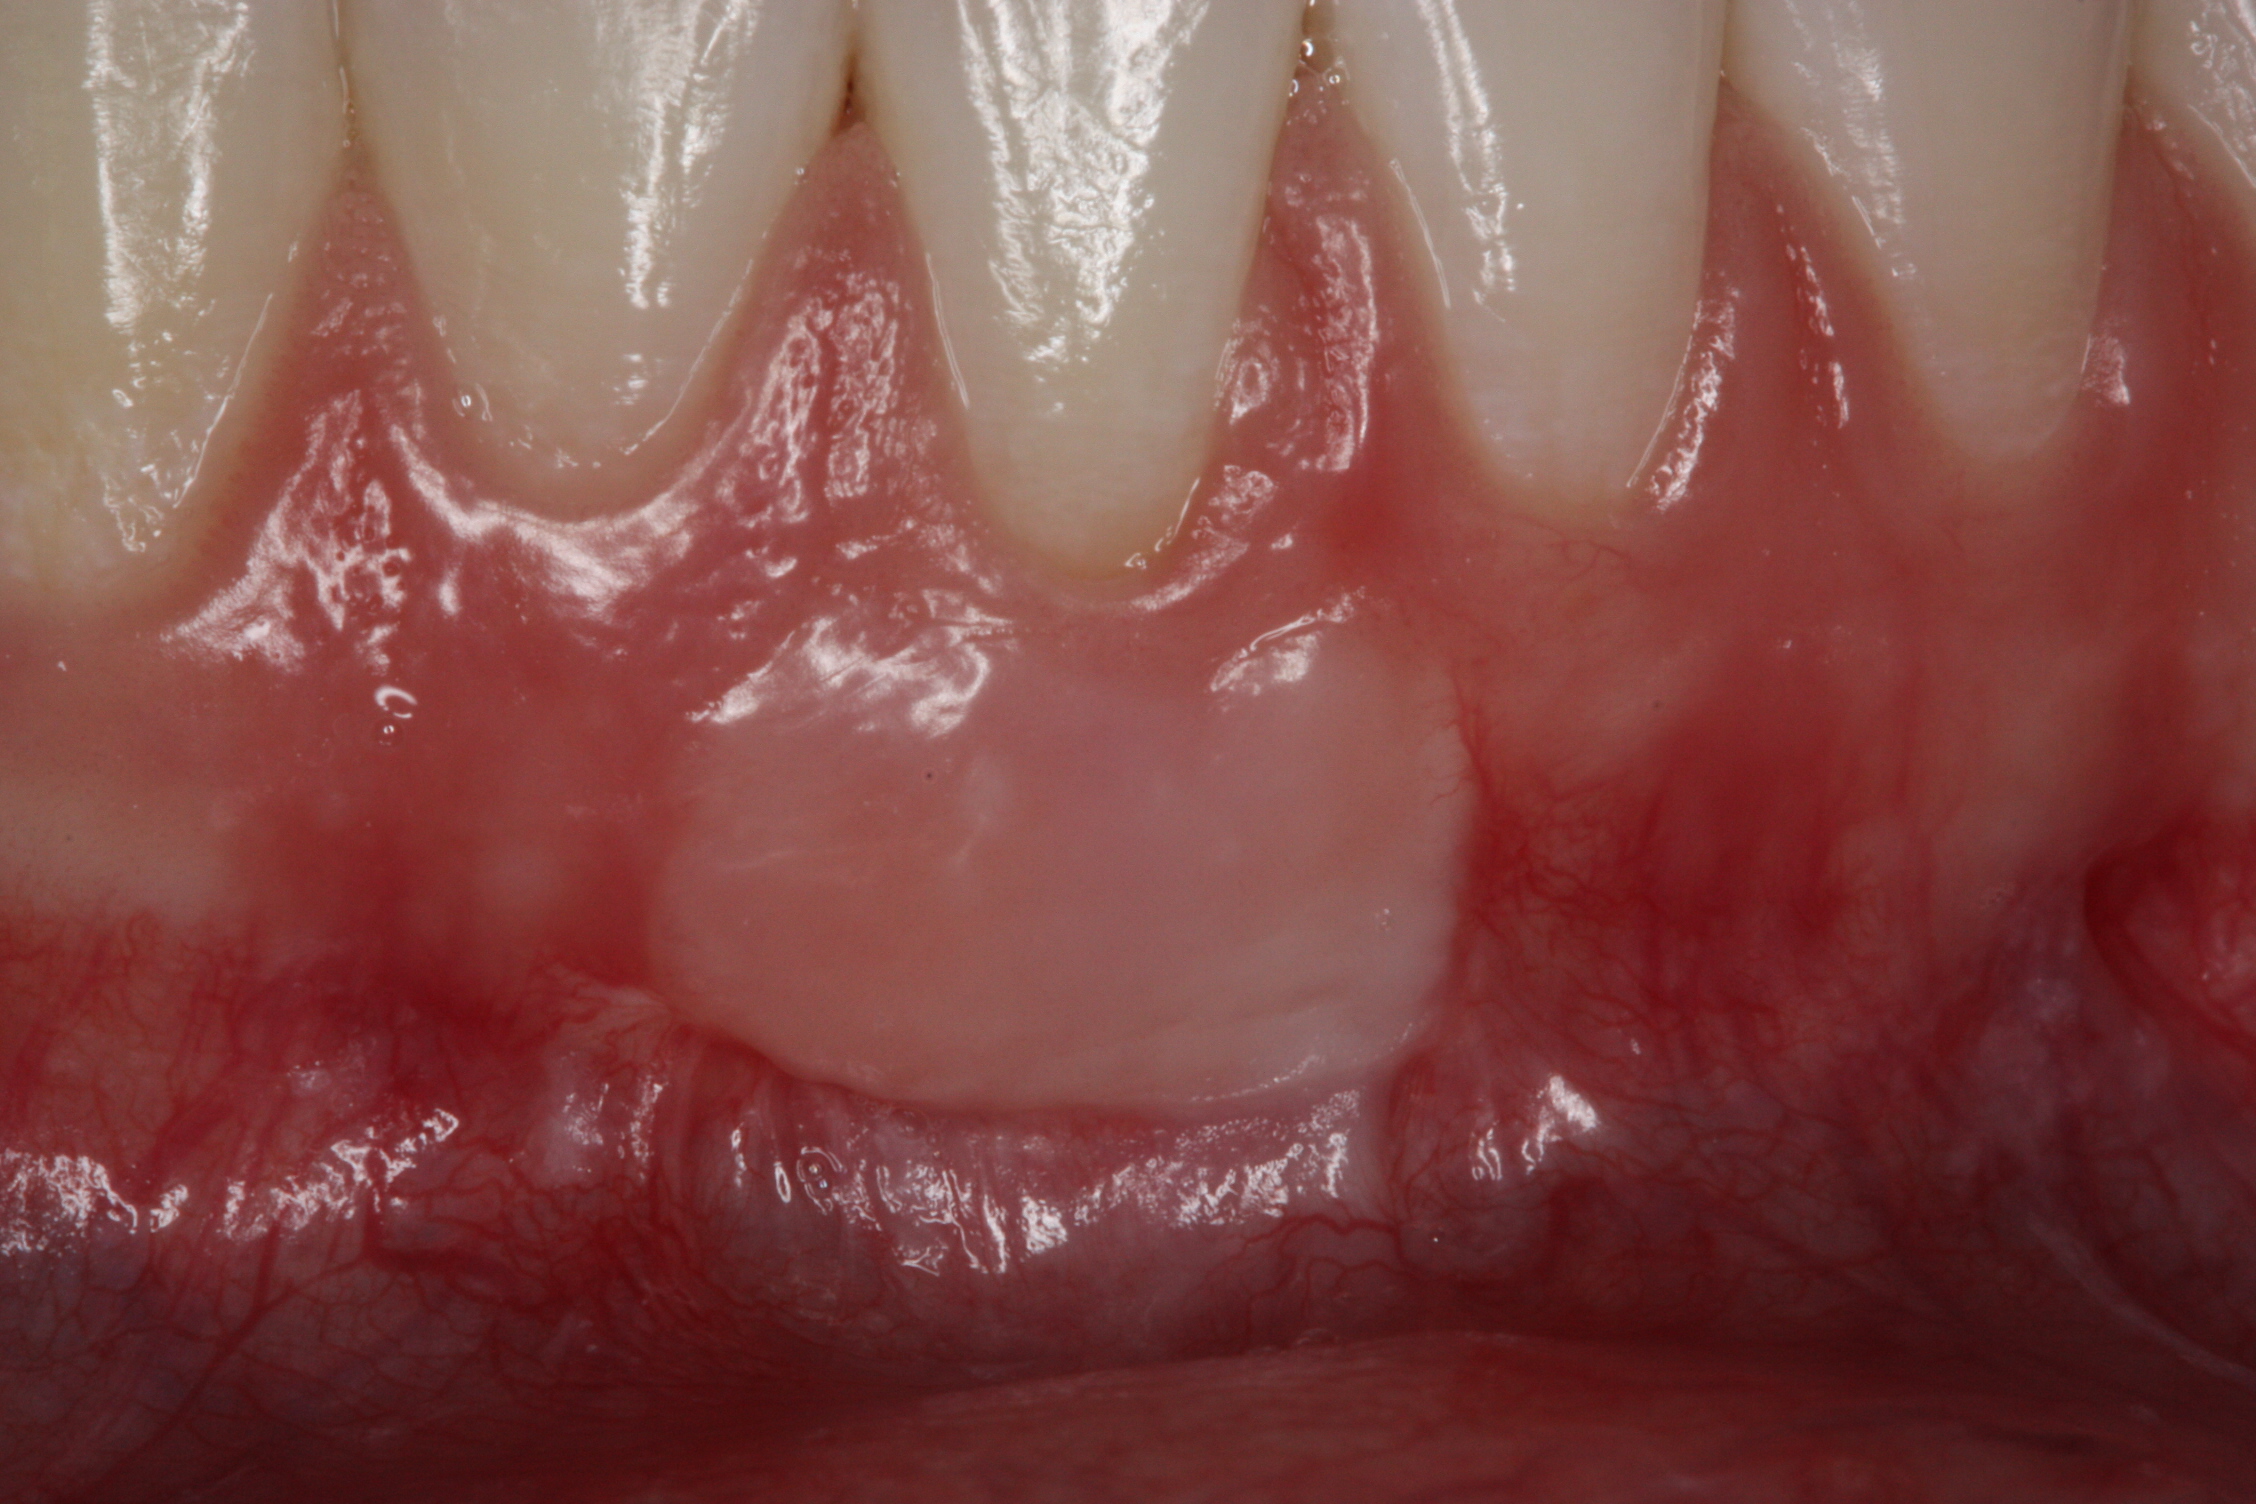

Various procedures to correct deficient gingival contours have been well documented in the dental literature.1,2 Increasing zones of attached gingiva using palatal donor tissue and the free gingival grafting procedure was introduced by Björn almost a half century ago.3 Using palatal donor tissue in the form of a free soft-tissue autograft for root-coverage procedures was reported by Miller.4 Additional procedures were reported using lateral5 or coronal repositioning6-8 of the adjacent attached gingiva via a pedicle flap or the coronal repositioning of previously grafted tissue.9,10 Miller also reported on gingival grafts placed over root surfaces to correct areas of deep-wide gingival recession.11 Further surgical advancements led to the use of subepithelial connective tissue from the palate to obtain root coverage.12-14 Figure 1 shows the pretreatment view of a mandibular central incisor, and Figure 2 depicts the post-treatment view of the site treated with a subepithelial connective tissue graft harvested from the patient’s palatal tissues.

Fig 1. Preoperative clinical view, mandibular central incisor.

Figure 1

Fig 2. Post-treatment clinical view after subepithelial connective tissue graft.

Figure 2